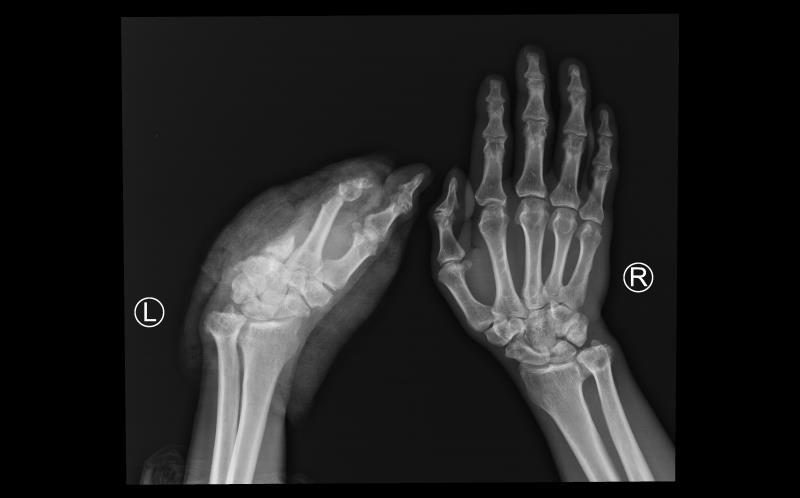

55岁的患者是西藏昌都人,8月9日下午,因车祸伤导致左手掌完全离断,因当地医院无再植医疗条件,经过初步处理后,采用疫苗冷链箱保存离断肢体,患者搭乘飞机于8月10日下午到四川省人民医院骨科急诊入院。

一般断肢再植的最佳时机是伤后6-8小时,而该患者来院时离断肢体缺血时间已经超过24小时,且车祸伤导致的残端不规则,再植手术难度大,术后出现并发症的风险高。

骨科肖成伟博士团队请示骨科胡豇主任,开展科内讨论后,决定冒着风险,做一次尝试性再植,给患者一次机会。经过积极的术前准备,在麻醉手术中心等相关科室的支持下,肖成伟博士团队很快开始了急诊再植手术。经过显微镜下长达6个半小时的奋战,一共吻合重建了3根动脉,6根静脉,5根神经,14根肌腱。8月11日凌晨2点,患者离断肢体恢复血供,再植手术获得初步成功。

术后一周,再植肢体安全度过了术后发生血管危象的可能。目前,再植肢体完全存活,其他功能也在逐步恢复中。据主刀医生介绍,康复后,患者虽然不能进行精细动作,但一般的生活自理是没问题的。